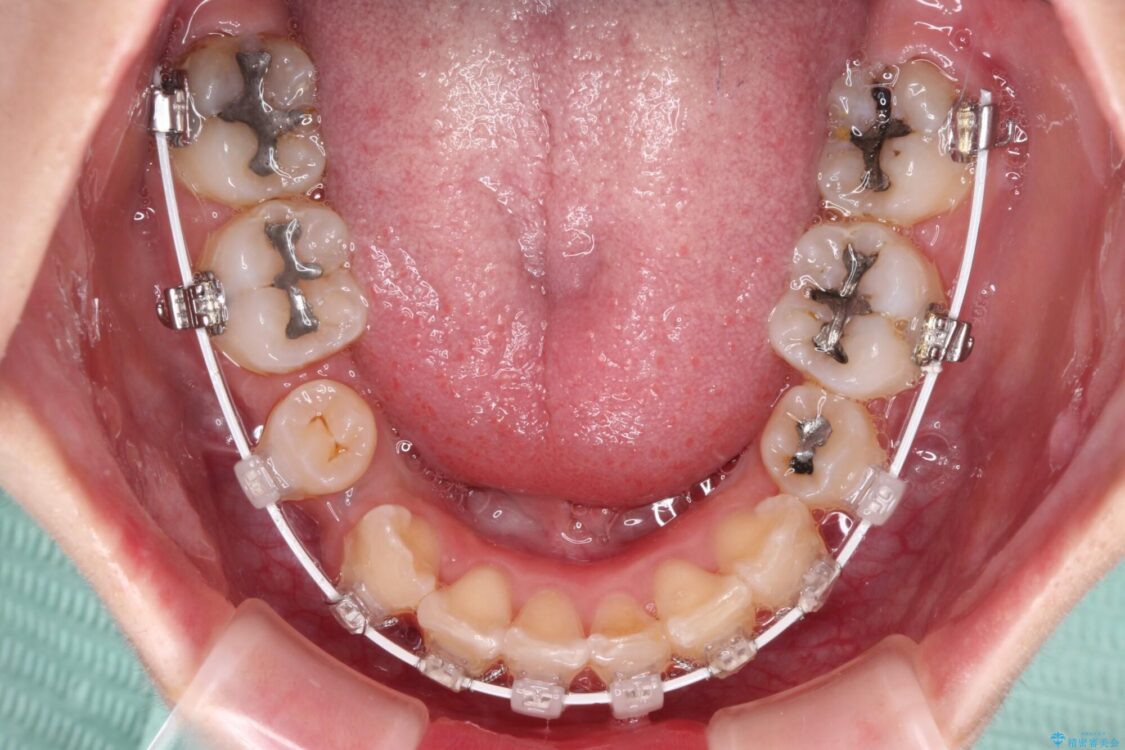

治療途中

• デコボコと深い咬み合わせ ワイヤー装置での抜歯矯正 治療途中画像